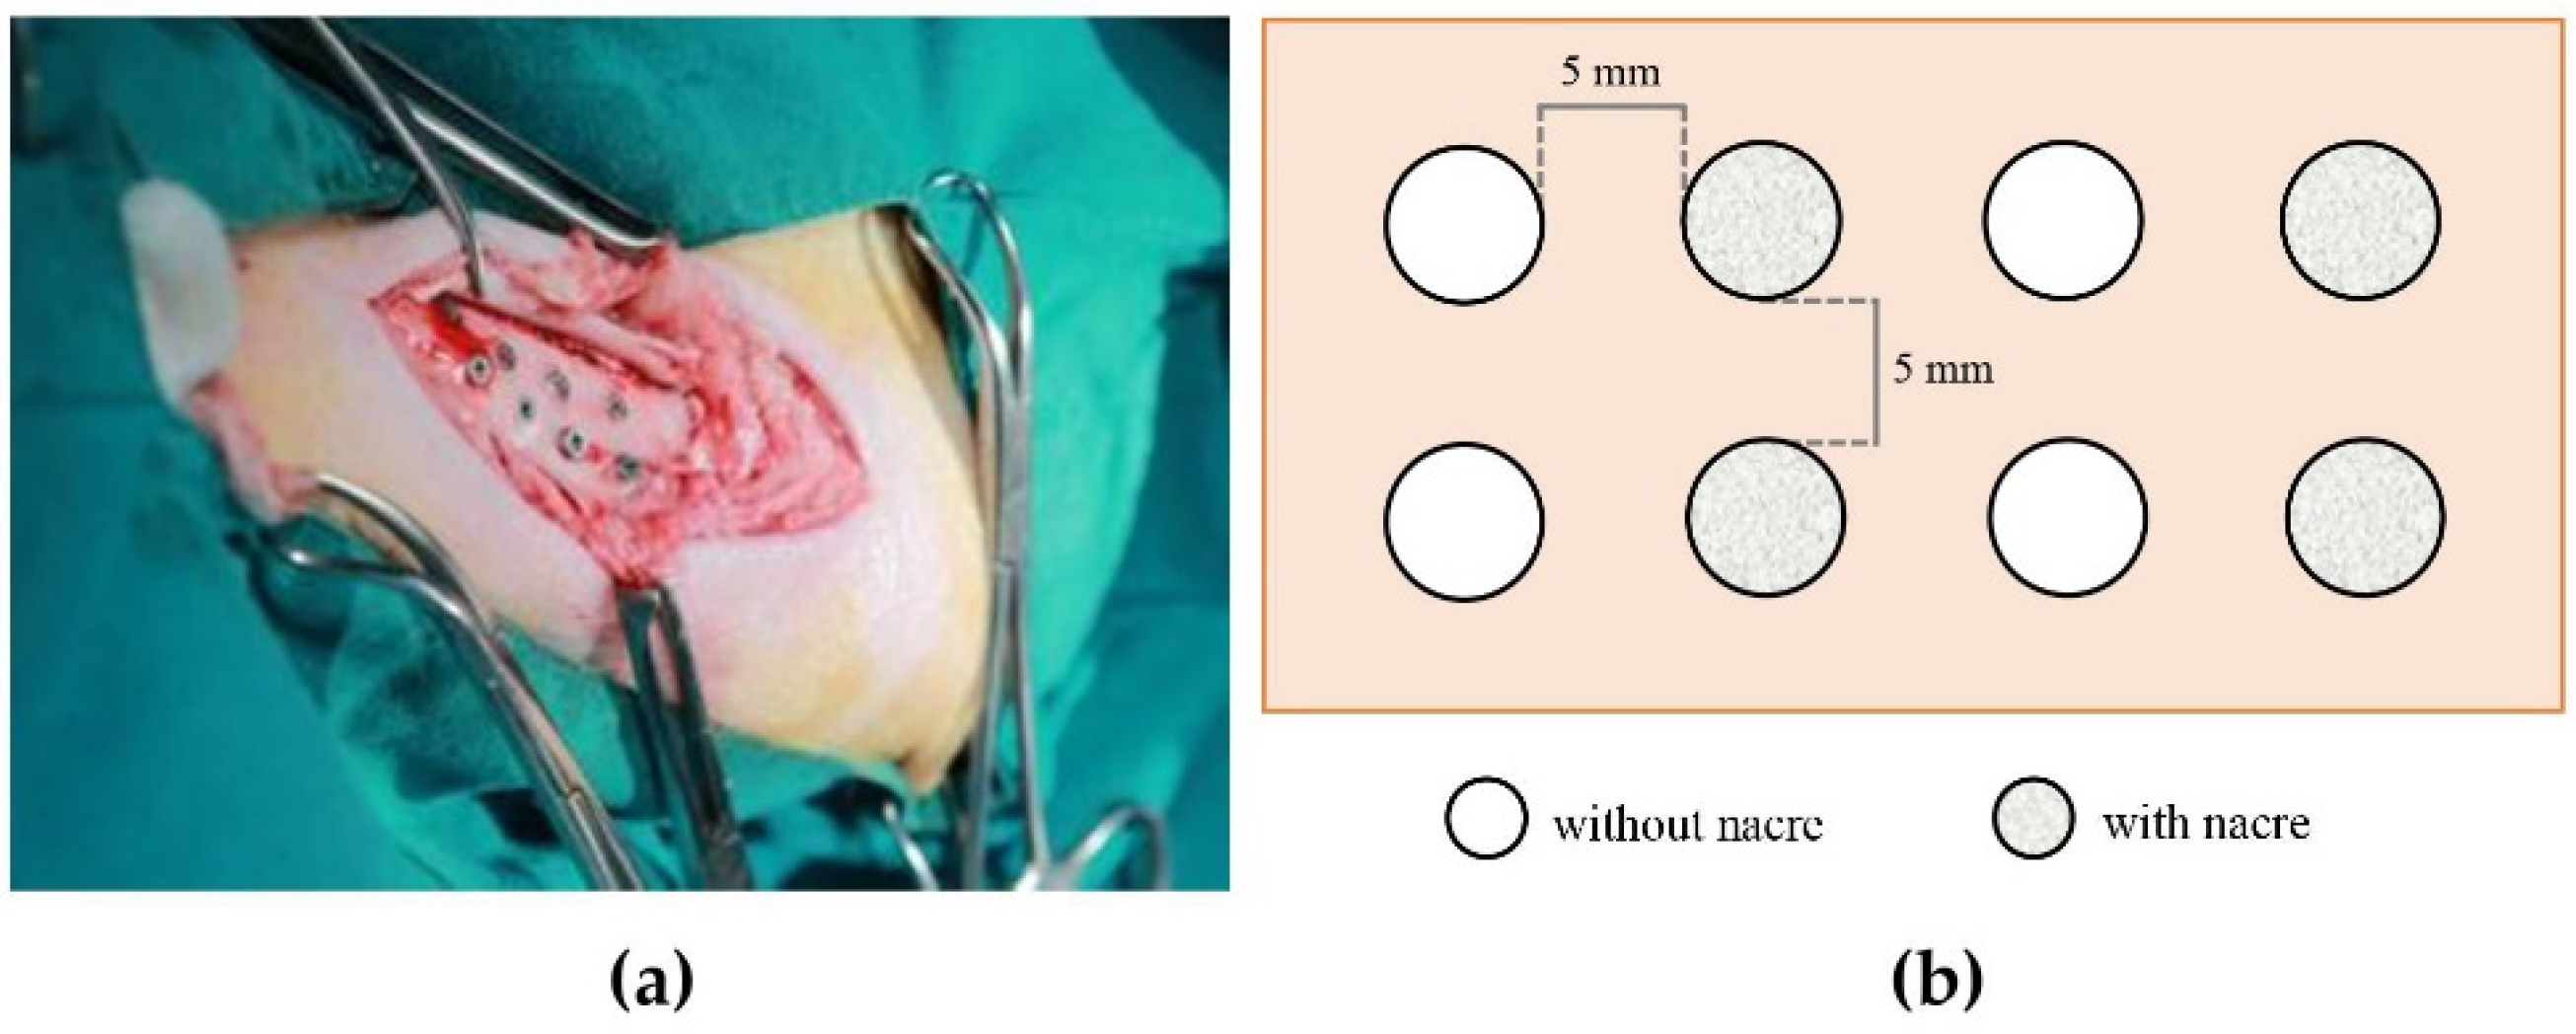

4.2. Animal Implantation